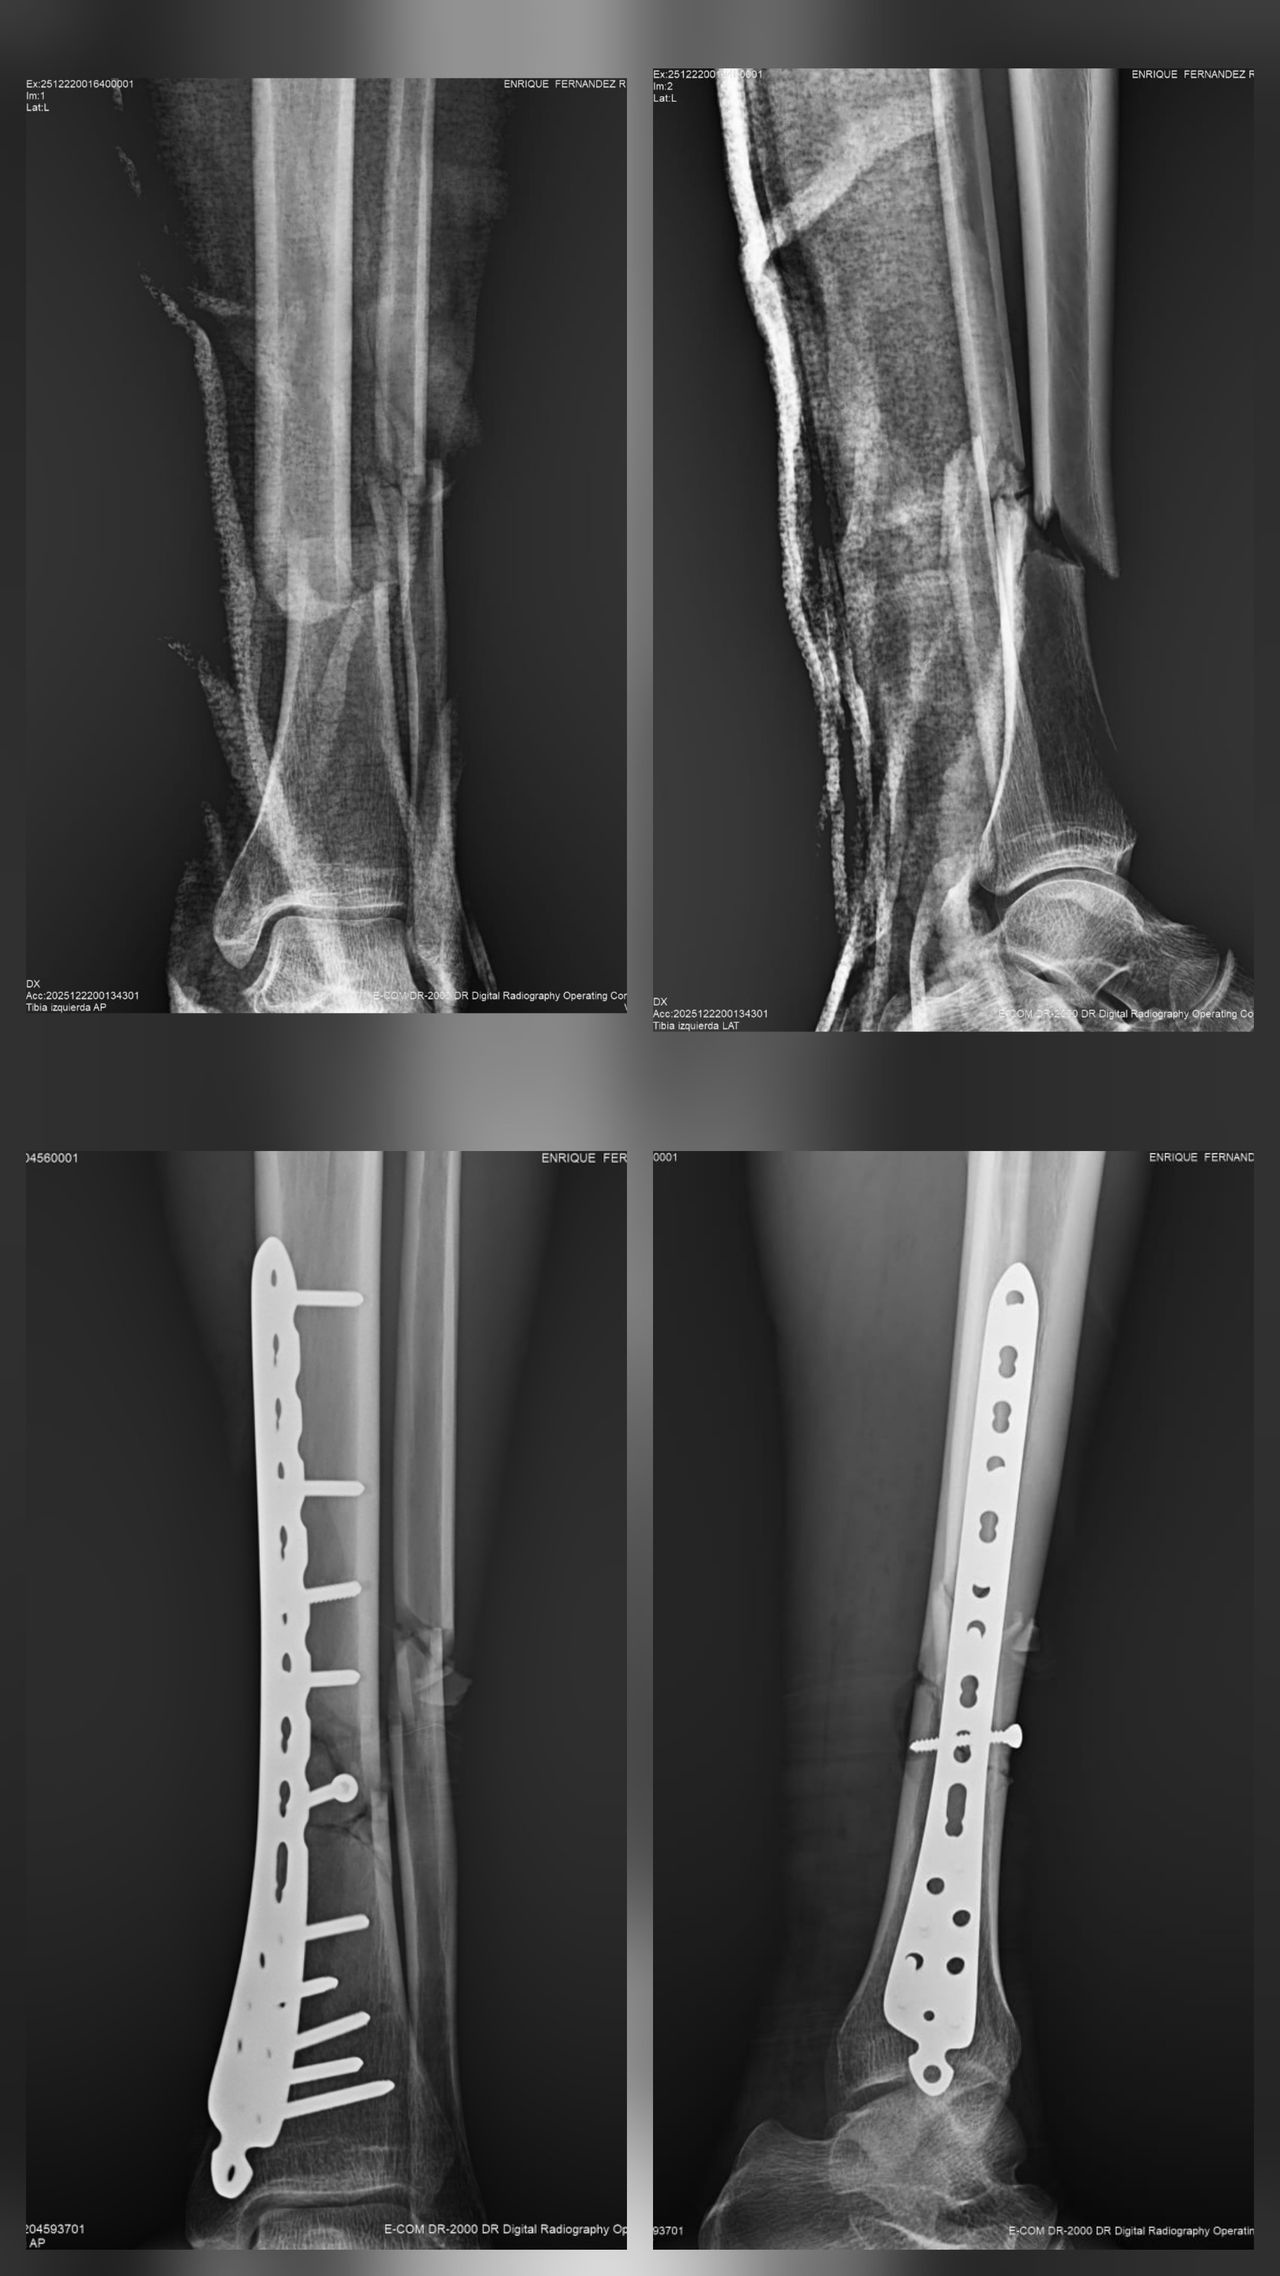

Mis habilidades más fuertes son el manejo de padecimientos de rodilla, cadera y hombro, así como procedimientos quirúrgicos asociadas a enfermedades degenerativas, fracturas y luxaciones.

Muy agradecida con las finas atenciones del Dr. Ramirez, resolvio oportunamente la fractura de mi mama, con insumos de primera calidad y gran sentido humano , se los recomiendo al mil.

• Consultorio 2 "Clínica San Alejandro" Inmovilización de fracturas y/o luxaciones de cadera, fémur y rodilla  •